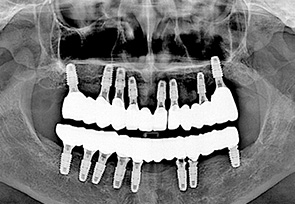

전악 임플란트는 치아가 완전히 없는 상태라도 잇몸뼈가 남아 있다면 임플란트를 여러개 심어 고정식으로 이를 해 넣을 수 있습니다. 잇몸 뼈에 단단히 고정되는 임플란트를 이용한 치료법으로 틀니를 사용할 때 보다 힘이 훨씬 좋고 내 치아 처럼 사용할 수 있습니다. 자연치아는 모두 28개 이지만 실직적으로 자연치아 개수만큼 다 심을 필요는 없습니다. 고정성 전악 임플란트를 위해서는 위 아래 턱 뼈와 맞물리게 되는 치아의 상태와 잇몸 뼈의 상태 등을 고려하여 임플란트를 식립하게 되며 보통 아래는 6~7개, 위에는 7~8개의 임플란트를 식립한 후 고정식으로 보철물을 결합하게 됩니다.

치료 케이스 보기

• after